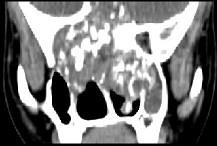

问题 男性,28岁,因鼻塞、头痛1年余,鼻窦CT扫描如图所示,请选择正确的描述与结论()

选项 A.双侧上颌窦、筛窦、鼻腔及蝶窦内见软组织肿块影 B.肿块内密度不均,有较多致密钙化影 C.窦壁及颅底骨质破坏 D.考虑鼻窦骨瘤 E.考虑为鼻窦软骨瘤

答案 ABCE